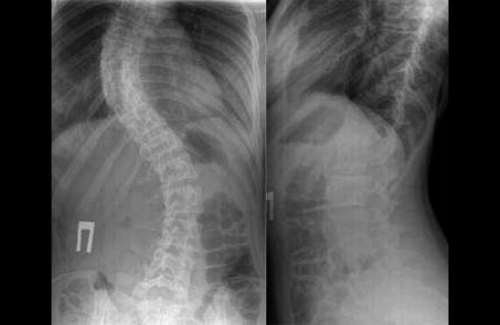

- рентгенография;

Рентгеновский снимок выполняется в двух проекциях. На его основе врач определяет степень искривления позвоночника в градусах, проводя линии на изображении и вычисляя угол патологического изгиба. При кифосколиозе часто требуется консультация невролога для проверки рефлексов, чувствительности и объема движений.

Диагноз кифосколиоз специалист выставляет на основании внешних признаков, а степень деформации определяет по данным рентгенографии позвоночника в двух проекциях. При визуальном осмотре грудной клетки определяется расширение межреберных промежутков на стороне, в которую отклоняется позвоночный столб.